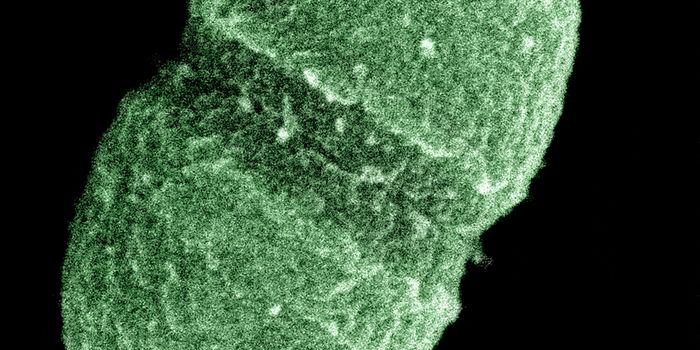

SEP 05, 2024Cell & Molecular BiologyCorynebacterium matruchotii ia a common bacterium that lives in human dental plaque; a colony is seen in this image by S ...